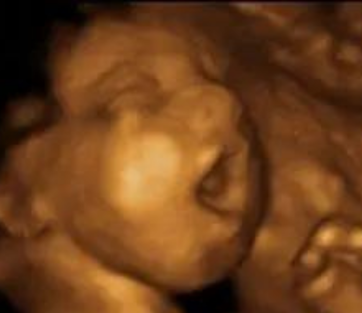

3D/4D

3D and 4D ultrasound are advanced imaging techniques use sound waves to create three-dimensional(3D) images or moving real-time 3D images(4D) of the developing baby